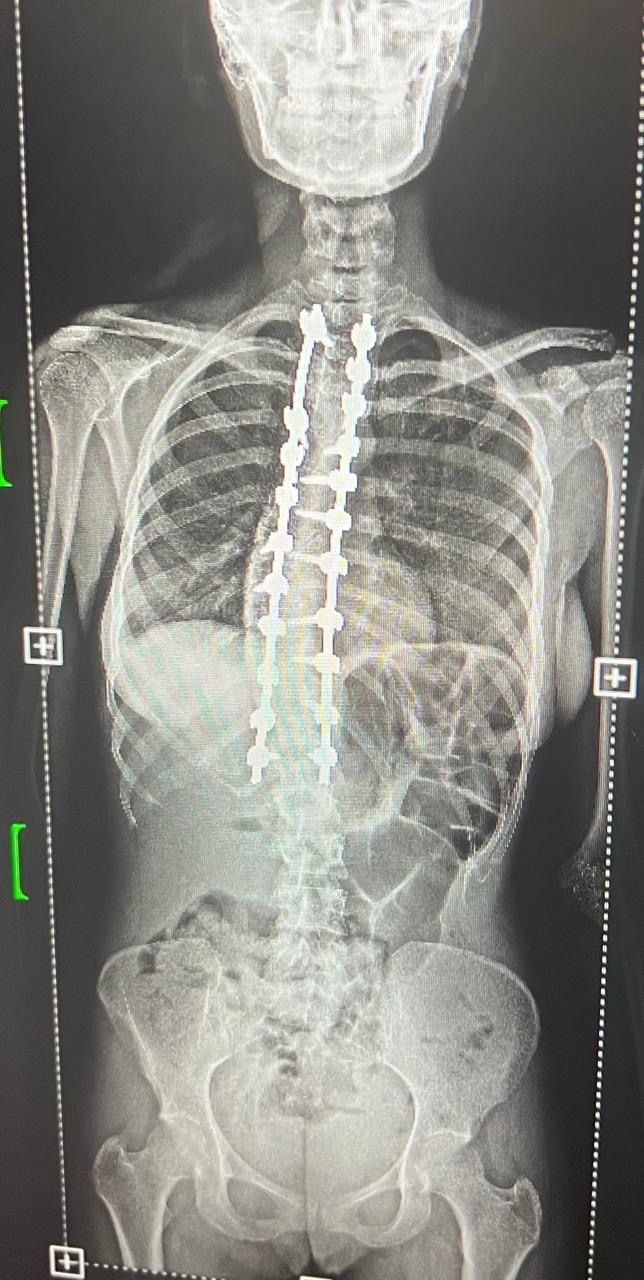

سجل مستشفى القطيف المركزي إنجازاً طبياً نوعياً بنجاح أول حالتين لتصحيح انحناء العمود الفقري، مستخدماً تقنيات المراقبة العصبية المتقدمة في جراحات استغرقت 8 ساعات.

وحقق قسم جراحة المخ والأعصاب والعمود الفقري بالمستشفى تقدماً لافتاً في التدخلات الجراحية الدقيقة، بعد تمكنه من إنهاء معاناة مريضين عبر إجراء عمليات تصحيح لانحناءات متقدمة في العمود الفقري لأول مرة.

وخضعت الحالتان لتقييم طبي شامل ودقيق تضمن إجراء كافة الفحوصات الإكلينيكية والأشعة المتخصصة، التي كشفت عن وجود تشوهات ودرجات انحناء متقدمة استوجبت التدخل الجراحي العاجل لتفادي المضاعفات.

واستعان الفريق الطبي بأحدث التقنيات العالمية في هذا المجال، معتمداً بشكل أساسي على أجهزة المراقبة العصبية الدقيقة لضمان أعلى معايير الأمان وسلامة الأعصاب الحساسة أثناء إجراء التعديل.

واستغرقت كل عملية نحو ثماني ساعات متواصلة من العمل الدقيق، نظراً لتعقيد الحالات وحاجتها لتنسيق عالٍ ولحظي بين جراحي العمود الفقري وفريق التخدير لضمان استقرار المريض.